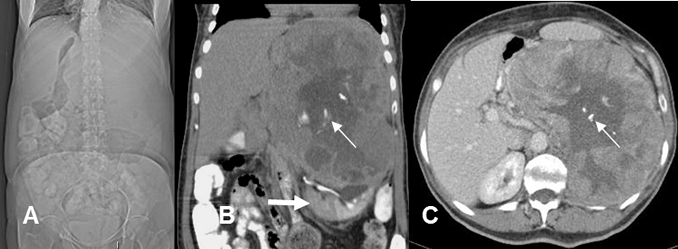

Fig 156 B. Angiosarcoma.

A: Rx AP. Efecto de masa, con desplazamiento medial e inferior de las asas intestinales.

B: TAC reconstrucción coronal y C: TAC axial. Masa heterogénea, que desplaza inferiormente el riñón izquierdo, (Flecha gruesa) con zona hipodensa central por necrosis. Además existen calcificaciones gruesas. (Flechas delgadas). No se identifica el bazo y la lesión corresponde a un angiosarcoma originado de este órgano.